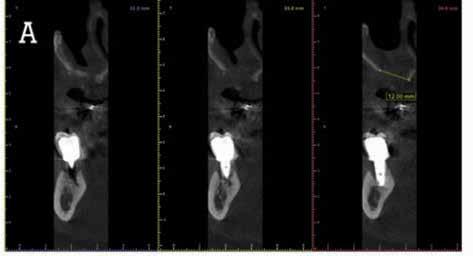

Proton density image of horizontally impacted tooth #17.

Proton density image of TMJ demonstrating anterior disc displacement, disc fold and joint effusion.